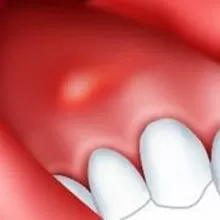

Причины и симптомы образования пародонтального абсцесса

Вышеприведенные симптомы должны насторожить пациента и побудить его обратиться за помощью в стоматологическую клинику. Если этого не сделать, то на следующем этапе между зубами и десной может появиться гной.

Причиной возникновения данного заболевания чаще всего является налет, в котором активно размножаются болезнетворные бактерии. При пародонтите поражаются не только мягкие ткани зуба, но также и костные ткани челюсти. Между зубом и десной образуются зубодесневые карманы, куда попадают остатки пищи. Самостоятельно вычистить карманы нельзя, поэтому они становятся постоянным очагом инфекции во рту.